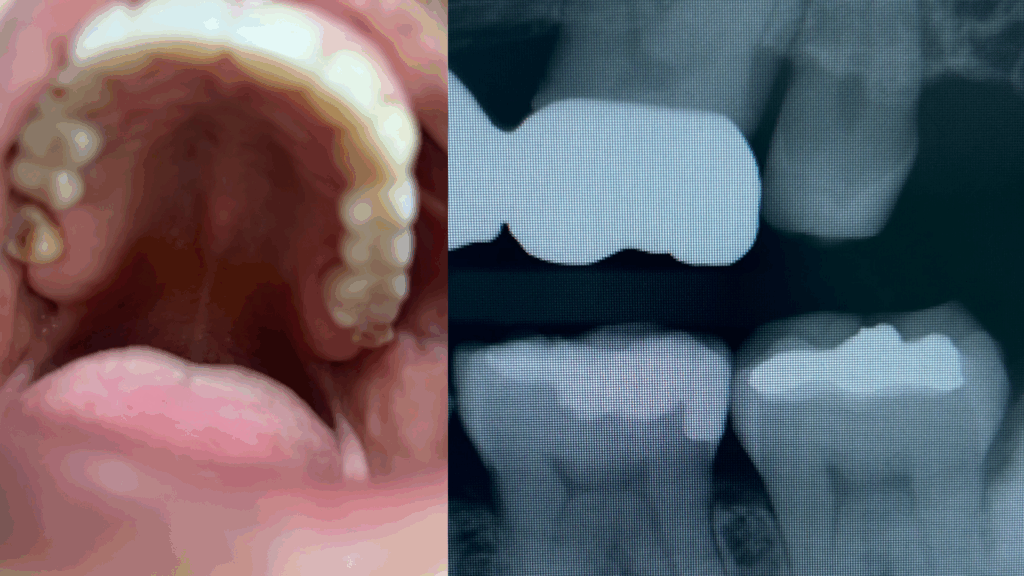

See, compare, and sharpen your clinical perception

Visual Lesion Identification Sessions

A focused training experience centered on pattern recognition and diagnostic clarity. Through comparative visuals, case-based learning, and structured frameworks, these sessions train clinicians to “see beyond the surface” and recognize oral lesions with accuracy, confidence, and a more intuitive clinical lens.